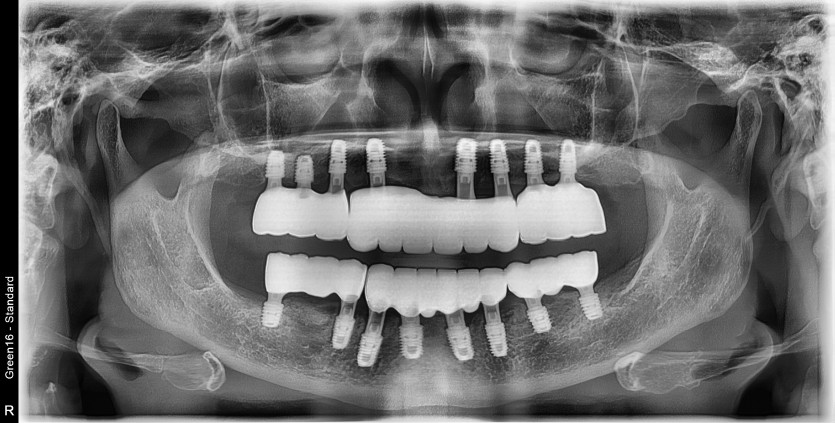

전체 임플란트 증례입니다.

16개의 임플란트로 완성하였습니다.